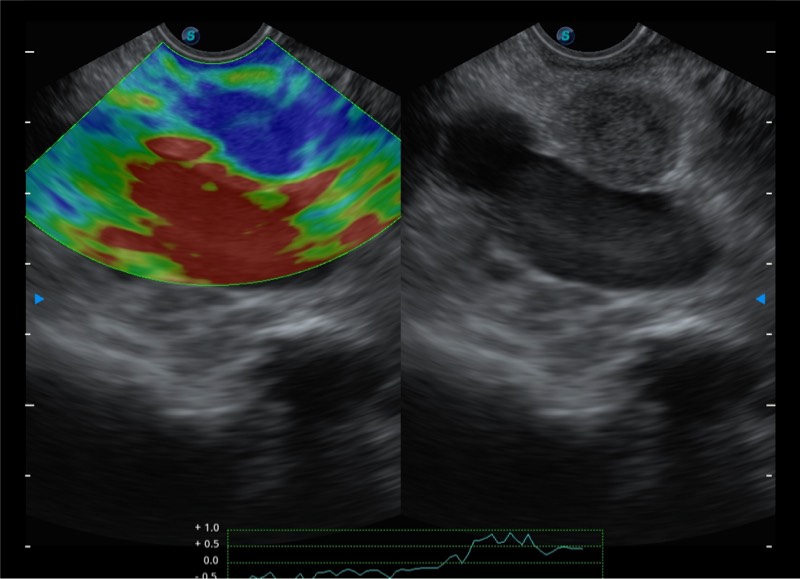

搭载百万级CMOS成像技术

及自主研发凸阵换能器,

可呈现优质的内镜和超声画面

基于二十年的超声技术积累,云顶集团官网提供了最新一代的独立超声主机,在提供高质量图像的同时满足多学科使用。具备常见多普勒技术并提供弹性成像、声学造影等高端影像技术。新一代传感器具有更强的抗干扰能力并减少图像伪影。